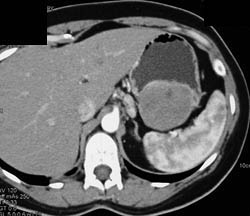

GIST Tumor With Ulceration